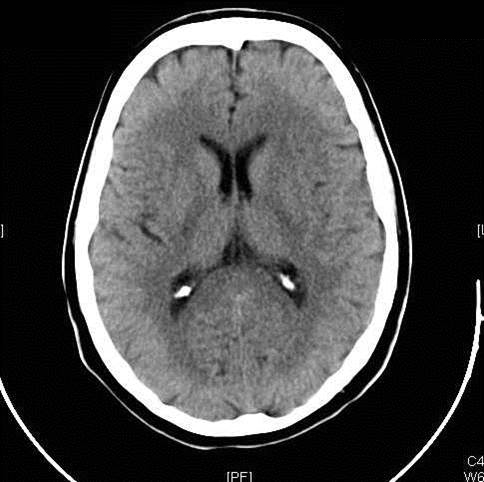

Figure 1: Ischemic Stroke. In an early acute ischemic cerebral stroke, a common finding is a normal CT scan since the brain tissue has not yet begun showing ischemic changes (left image). The middle image shows a diffusion weighted image (DWI) of a right hemispheric stroke (white area), and a CT angiogram shows the cause to be a blockage of the right middle cerebral artery (MCA), seen as a lack of blood vessel flow on the right side of the brain (left side of image). Poor blood flow is also seen in the right internal carotid artery due to stenosis from atherosclerosis. (Images courtesy of Dr. McMurtrey)